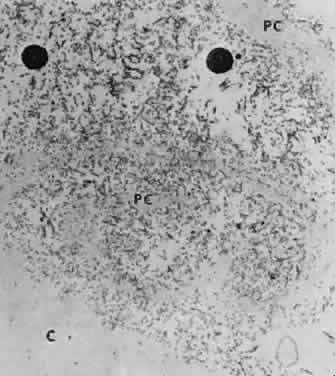

Fig. 10. Scanning electron micrograph showing layer of anterior lens capsule and exfoliative material (PC) peeling back from rest of capsule. Asterisks indicate exfoliative vegetations (× 5340). (Dark AJ, Streeten BW, Cornwall CC: Pseudoexfoliative disease of the lens: A study in electron microscopy and histochemistry. Br J Ophthalmol 61:466,1977)

Fig. 11. Transmission electron micrograph of peeling lens capsule (PC) rolled up in spiral, enclosing masses of exfoliative fibers and two melanin granules. C, main capsule (× 14,600). (Courtesy of Dr. Barbara Streeten)